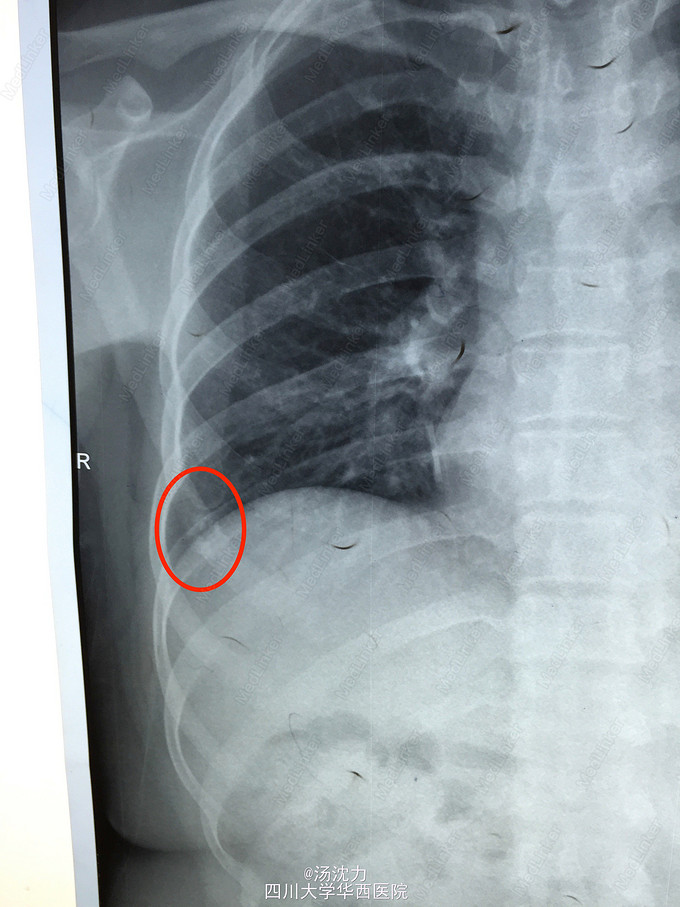

肋骨转移还是陈旧性骨折?

患者乳腺癌术后规律复查,未诉骨折病史及明显不适。最近三年胸片如图。2年前曾行骨扫描,怀疑该处为陈旧性骨折。

2年前和1年前的病变比较起来比较像骨折修复的感觉,但是今年的胸片变化看着又像是明显的溶骨改变,加上患者未诉明显的外伤史,所以更倾向于怀疑是转移瘤。